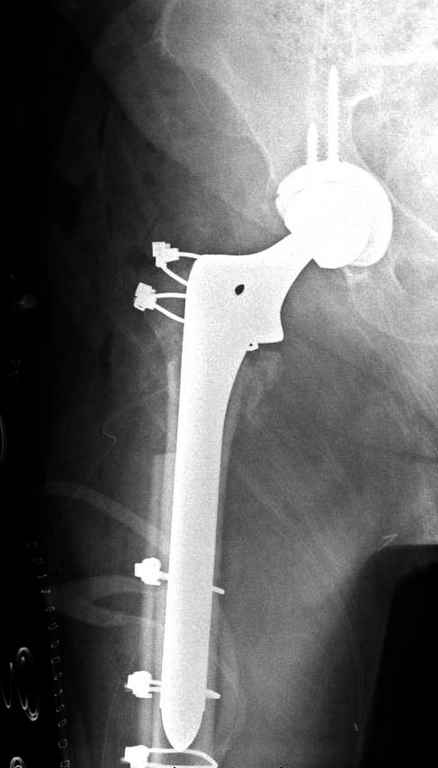

В приложении похожий пример, к счастью, пациентка появилась не после, а "за полчаса" до протрузии. Пересинтезировали с исправлением ошибок.

В данном случае в головке бедра и в вертлужной впадине огромный дефект, навряд ли удалением импланта или заменой на другой можно сохранить сустав.

Вашему вниманию представляется похожий случай, пациентке 70, осложнился в течение одного месяца после операции. Ревизия с заменой сустава, кабельная фиксация на трохантер. При установке в дистальном диафизе обнаружен тонкий кортикальный слой и сделана профилактика от возможного перелома аллографтом.